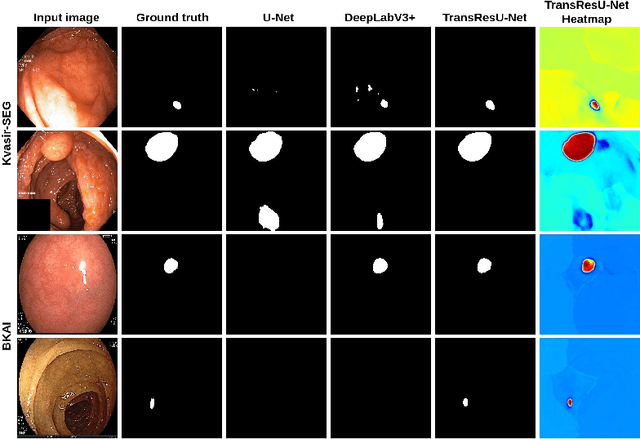

TransResU-Net: Transformer based ResU-Net for Real-Time Colonoscopy Polyp Segmentation

Jun 17, 2022

Colorectal cancer (CRC) is one of the most common causes of cancer and cancer-related mortality worldwide. Performing colon cancer screening in a timely fashion is the key to early detection. Colonoscopy is the primary modality used to diagnose colon cancer. However, the miss rate of polyps, adenomas and advanced adenomas remains significantly high. Early detection of polyps at the precancerous stage can help reduce the mortality rate and the economic burden associated with colorectal cancer. Deep learning-based computer-aided diagnosis (CADx) system may help gastroenterologists to identify polyps that may otherwise be missed, thereby improving the polyp detection rate. Additionally, CADx system could prove to be a cost-effective system that improves long-term colorectal cancer prevention. In this study, we proposed a deep learning-based architecture for automatic polyp segmentation, called Transformer ResU-Net (TransResU-Net). Our proposed architecture is built upon residual blocks with ResNet-50 as the backbone and takes the advantage of transformer self-attention mechanism as well as dilated convolution(s). Our experimental results on two publicly available polyp segmentation benchmark datasets showed that TransResU-Net obtained a highly promising dice score and a real-time speed. With high efficacy in our performance metrics, we concluded that TransResU-Net could be a strong benchmark for building a real-time polyp detection system for the early diagnosis, treatment, and prevention of colorectal cancer. The source code of the proposed TransResU-Net is publicly available at https://github.com/nikhilroxtomar/TransResUNet.